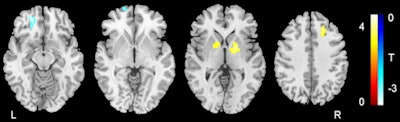

In reviewing the resting-state fMR images, Li and colleagues found significant ALFF abnormalities in five brain regions in the ADHD patients compared with the control subjects.

More specifically, patients with ADHD showed impaired executive function, along with the following:

- Lower ALFF in the left orbitofrontal cortex and the left ventral superior frontal gyrus

- Higher ALFF in the left globus pallidus, the right globus pallidus, and the right dorsal superior frontal gyrus

- Lower long-range functional connectivity in the frontoparietal and frontocerebellar networks

- Higher functional connectivity in the frontostriatal circuit that correlated across subjects with ADHD with the degree of executive dysfunction